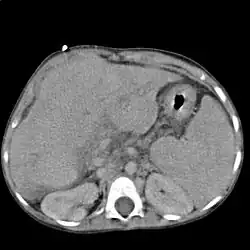

Диагностика

Характерно повышение активности АЛТ, АСТ, щелочной фосфатазы, лейкоцитоз. При гепатолиенальном синдроме может развиваться гиперспленизм, проявляющийся лейкопенией, тромбоцитопенией, анемией и увеличением клеточных элементов в костном мозге.

Расширенные и извитые венозные коллатерали выявляются при ангиографии, компьютерной томографии, ультразвуковом исследовании или в ходе оперативного вмешательства.